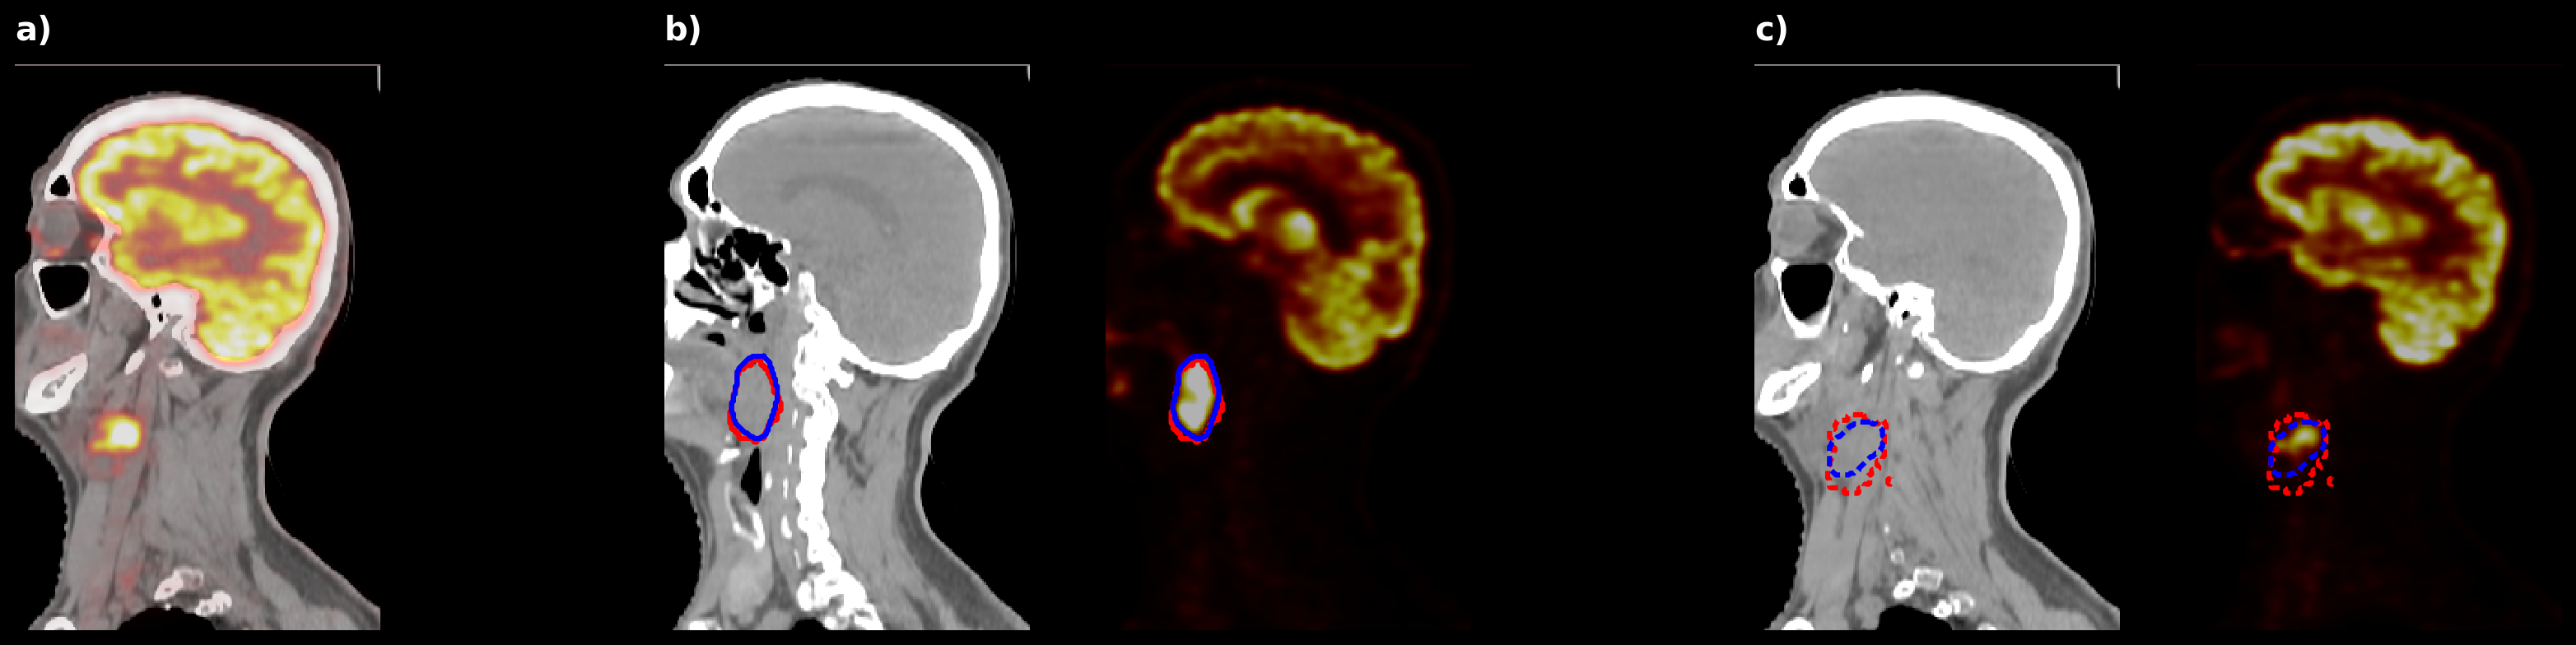

As detailed in Table 3, the SegResNet model achieved the best overall performance, with a mean DSC of 0.6660±0.01990.6660\pm 0.0199 for primary tumors and an aggregated DSC of 0.7291±0.00920.7291\pm 0.0092 for nodal metastases. Figure 6 provides qualitative visualization. These results confirm the dataset’s high quality and suitability for training and validating robust segmentation algorithms.

Refer to caption

Figure 6: Segmentation results from the SegResNet model. (a) Preprocessed sagittal CT slice with PET overlay after head–neck cropping. (b) Primary tumor slice with ground truth (red) and prediction (blue) contours (solid). (c) Lymph node slice from a different location with ground truth and prediction contours (dashed).